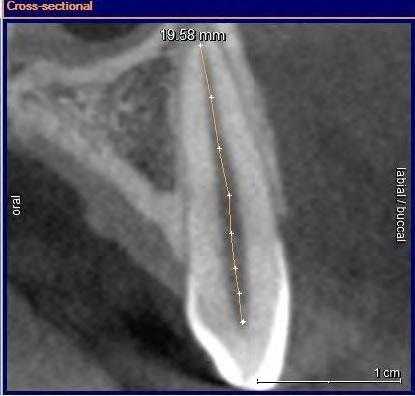

Качество пломбирования 4.7 зуба, по данным КЛКТ, было неудовлетворительным. В мезиально-щечном и дистальных каналах 4.7 зуба пломбировочный материал прослеживался в виде отдельных фрагментов (рис. 3) . Мезиально-язычный канал обтурирован неплотно, до апикальной стриктуры (рис. 4). Наблюдали признаки апикальной резорбции дистального корня (рис. 5) .

Рис. 3. КЛКТ, косо-сагиттальная и корональная томограммы мезиального корня 4.7 зуба. Выведен мезиально-щечный канал 4.7 зуба.

Рис. 4. КЛКТ, косо-сагиттальная и корональная томограммы мезиального корня 4.7 зуба. Выведен мезиально-язычный канал 4.7 зуба.

Рис. 5. КЛКТ, косо-сагиттальная и корональная томограммы дистального корня 4.7 зуба.

С изобретением нового программного обеспечения для КЛКТ Orthophps CG3D/Galelios (Sirona, Germany) рабочая длина каналов также стала осуществляема. Но точность этих данных в клинической работе еще должна быть подтверждена (Фото 3).

Фото 3: Инструмент для измерения длинны корневого канала

![]()